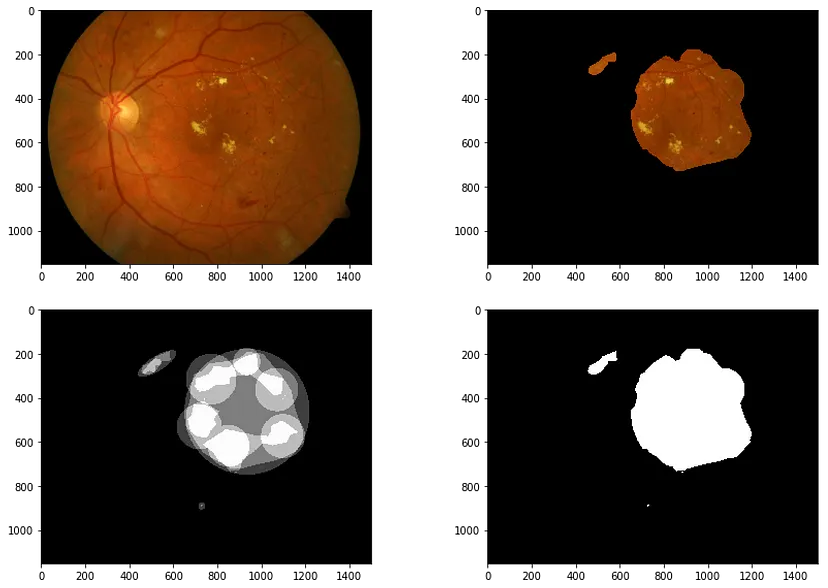

使用共识掩码隔离 ROI:根据原始 ROI 注释(左下)生成至少两位专家投票的共识掩码(右下)。此掩码用于将感兴趣的区域与眼底检查图像(左上)隔离,从而生成掩码图像(右上)。

我们从一些图像处理开始,即细化感兴趣的区域。每张图像都由四位专家标记,从而创建了一个蒙版。我们可以对蒙版进行阈值处理,以要求一定数量的专家达成共识,这是带注释的研究图像中广泛使用的技巧(如果您不熟悉它,请滚动到底部!)。然后,我们使用硬性渗出液相对突出的亮黄色将它们转换为 GNG 可以开始表征的数据点(有关细节,请参阅配套笔记本,其中解释了一些额外的技巧,包括一些形态变换)。

使用 OpenCV 的颜色阈值功能从原始 ROI 中提取硬脂质渗出物。只有落在特定色调角度范围内的值才会被保留。经过一些形态学操作以消除噪音后,我们留下了一个布尔图像,该图像将转换为二进制网格格式,以供 GNG 进行训练。